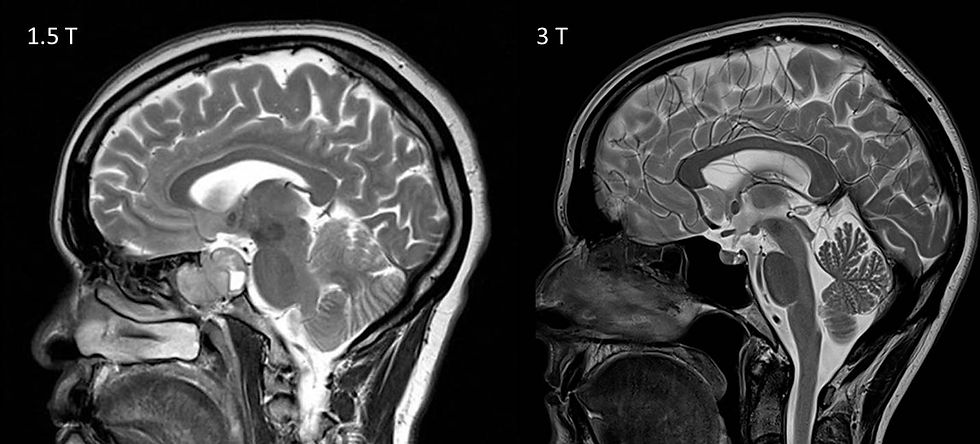

На сегодняшний день в клинической практике наиболее широко используются томографы с напряжённостью магнитного поля 1,5 Тесла (Тл) и 3 Тесла. Однако, вопреки распространённому мнению, что "чем выше мощность, тем лучше", вопрос не так однозначен. Повышение напряжённости магнитного поля действительно даёт определённые преимущества — в первую очередь, в виде увеличения сигнала и разрешения — но вместе с этим появляются и новые физические, технические и клинические ограничения, которые необходимо учитывать при выборе аппарата МРТ.

Важно понимать, что 3 Тесла — это не "в два раза лучше", чем 1,5 Тесла. Более того, в некоторых сценариях высокопольный аппарат МРТ может не только не дать диагностических преимуществ, но и усложнить проведение исследования или снизить его воспроизводимость. Кроме того, эксплуатационные аспекты, такие как чувствительность к артефактам, тепловая нагрузка (SAR), стоимость обслуживания и требовательность к условиям помещения, становятся критически важными при принятии окончательного решения.

Степень поляризации ядер — ключевой фактор, определяющий амплитуду сигнала. Согласно уравнению Больцмана, избыточная намагниченность пропорциональна напряжённости магнитного поля B₀. Таким образом, при переходе от 1,5 Тесла к 3 Тесла наблюдается приблизительно линейный рост амплитуды сигнала, то есть сигнал возрастает в ~2 раза. Однако на практике улучшение соотношения сигнал/шум (SNR) оказывается нелинейным.

SNR — это один из фундаментальных параметров, определяющих качество МР-изображения. Теоретически, при увеличении B₀ с 1,5 до 3 Тесла, SNR увеличивается на 40–100%, в зависимости от исследуемой анатомической области, типа катушек, последовательности и пространственного разрешения. Наиболее выраженный прирост наблюдается в головном мозге, орбите, позвоночнике и крупных суставах.

Таким образом, выигрыш от 3 Тесла — это не «в два раза лучше», а «в два раза больше возможностей для компромисса» между качеством, скоростью и безопасностью. В реальной клинической практике, например, разрешение при 3 Тесла может быть увеличено на 20–30% при сохранении времени сканирования, либо, наоборот, исследование проводится быстрее на 30–50% при сохранении диагностического качества.